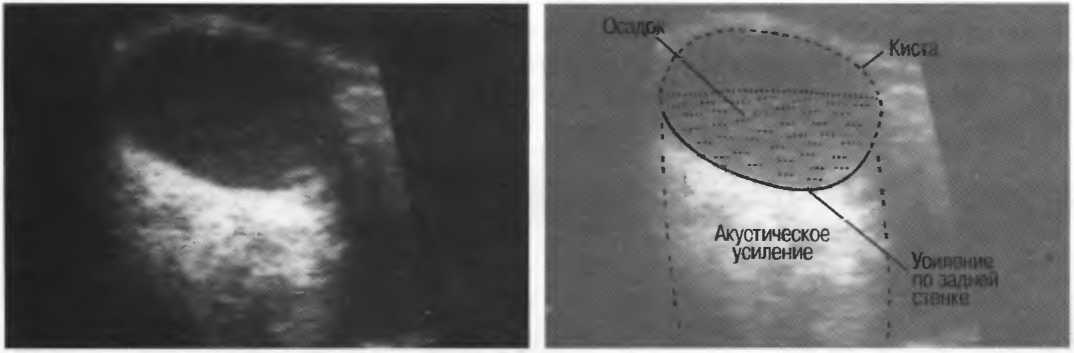

Осадок в кисте может флотировать, формируя уровень, изменяющий свое положение при перемещении пациента (рис. 16б,в).

Рис. 16б. Киста с усилением по задней стенке, латеральными тенями и осадком в полости.

Рис. 16в. Этот же пациент, что и на рис. 16б. Сканирование осуществляется в разных положениях больного. Уровень, создаваемый осадком, смещается.